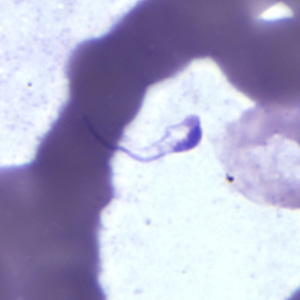

Platelets.

Elongated and degenerating platelets in blood may be confused for Trypanosoma spp. or malaria elements.

Figure A: Platelet in a thick blood smear. The nature of the platelet gives it the appearance of a trypomastigote of Trypanosoma sp.

Figure B: Platelet in a thin blood smear. The nature of the platelet gives it the appearance of a trypomastigote of Trypanosoma sp.